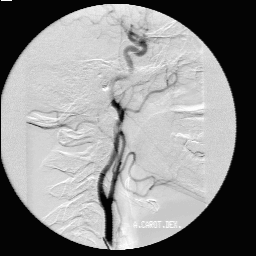

Для решения данных проблем разработана следующая схема передачи данных из ультразвуковой медицинской диагностической установки в персональный компьютер. (плакат 1) Я осуществлял подключение ультразвуковой диагностической установки ALOCA SSD 650. Она осуществляет срез информации органов исследуемого пациента на глубину до 30 см. от места контакта с телом пациента и работает на частоте от 2 до 7,5 мГц. И выводит информацию на экран с разрешением 640 * 480 с 64 уровнями градации серого. Полученная информация преобразуется в стандартный видеосигнал, который может быть снят с специализированных выходов. Захват и обработку информации из ультразвуковой медицинской установки осуществляется устройством, называющимся frame grabber. Оно позволяет в «реальном времени» преобразовать видеосигнал в цифровое изображение и сохранить его в персональном компьютере. К frame grabber’у предъявляется ряд характерных требований. Это должно быть устройство, позволяющее длительную оцифровку видеосигнала в реальном времени, обладать высокоскоростной «шиной», для быстрой передачи полученной информации в персональной компьютер. В нем должна быть предусмотрена возможность настройки яркости и контрастности для первоначальной настройки при подключении к медицинской диагностической установке и оно должно быть совместимо со всеми основными современными операционными системами. Всем этим требованиям удовлетворяет frame grabber HI*DEF PLUS фирмы IMAGRAPH. Данный frame grabber позволяет получать 256 уровней градации серого, что позволяет иметь запас по разрешению изображения для ультразвуковых медицинских установок более высокого класса и получать изображения, над которыми можно производить определенные операции. Кроме того, это сравнительно недорогое устройство, в своем классе, что является преимуществом, т.к. наши медицинские учреждения финансируются не достаточно. Frame grabber передает информацию в передает информацию в персональный компьютер первичного пользователя. Оптимальной конфигурацией персонального компьютера первичного пользователя является P2 – 400, 128, 4.3 + 18 SCSI, 8 V I740. Данная конфигурация предоставляет возможность осуществлять захват изображения из ультразвуковой медицинской диагностической установки, поддерживать режим телеконференций, осуществлять передачу получаемого сигнала по сети в реальном времени и обрабатывать получаемую информацию. Но т.к. парк персональных компьютеров в медицинских учреждениях России, на данное время, состоит из персональных компьютеров устаревших моделей, то в этом случае можно использовать лишь основные функции - захват и обработку изображений. Это можно осуществлять на персональных компьютерах класса DX4 – 100 с 16 мБ оперативной памяти, размером жесткого диска 800 мБ и сетевой картой NE2000 или совместимой. Персональный компьютер первичного пользователя позволяет передавать полученную информацию по компьютерной сети. Вопросы передачи информации по компьютерной сети подробно рассматриваются в дипломном проекте Еремеева Артема, который также выполнял дипломную работу в рамках проекта «телемедицина». К персональному компьютеру вторичного пользователя предъявляются те же требования, что и к персональному компьютеру первичного пользователя, за исключением того, что у в нем не устанавливается frame grabber для захвата изображения с ультразвуковой медицинской диагностической установки. В результате захвата изображения получается файл в котором необходимо отобразить не только информацию собственно о картинке, но и дополнительную. Для этого был разработан формат файла плакат 2 , который содержит в себе следующие поля:

Информационное поле данного файла на прямую связано с характеристиками ультразвуковой медицинской диагностической установки, frame grabber’а и персональным компьютером. В рамках данной работы, в результате взаимодействия с медицинским персоналом, возникла необходимость преобразования изображений для выделения областей, контуров этих областей, границ образований. Для этого мною были внедрены ряд фильтров. Это сглаживающий фильтр, медианный сглаживающий фильтр, контурный фильтр и полутоновой фильтр. Результаты воздействия данных фильтров на изображение можно наблюдать плакат 3. По результатам консультирования с врачами, было выявлено, что их применение дает наиболее хороший эффект при последовательном воздействии на изображение нескольких фильтров. Это можно наблюдать на плакате 4. Это было апробировано специалистами и было выявлено, что результаты воздействия этих фильтров на изображение несут в себе высокую практическую ценность. В данной дипломной работе было: